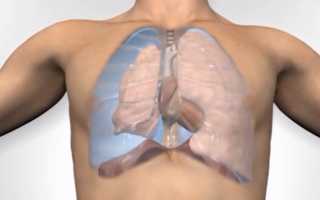

Из широкого спектра фтизиохирургических операций наибольшее значение в современной практике имеют резекции легких и пневмонэктомии, позволяющие сразу же ликвидировать легочные деструкции. Быстрота ликвидации полости особенно важна, поскольку с момента образования каверны именно она становится основным источником инфекции и прогрессирования, а ее ликвидация является главным в излечении туберкулеза.

Пневмонэктомия (удаление легкого) применяется при туберкулезе сравнительно нечасто (3—6% случаев всех фтизиохирургических операций, выполняемых в РФ), однако она является самым рискованным и травматическим вмешательством. Первая успешная пневмонэктомия в нашей стране выполнена J1.K. Богушем в 1947 г.